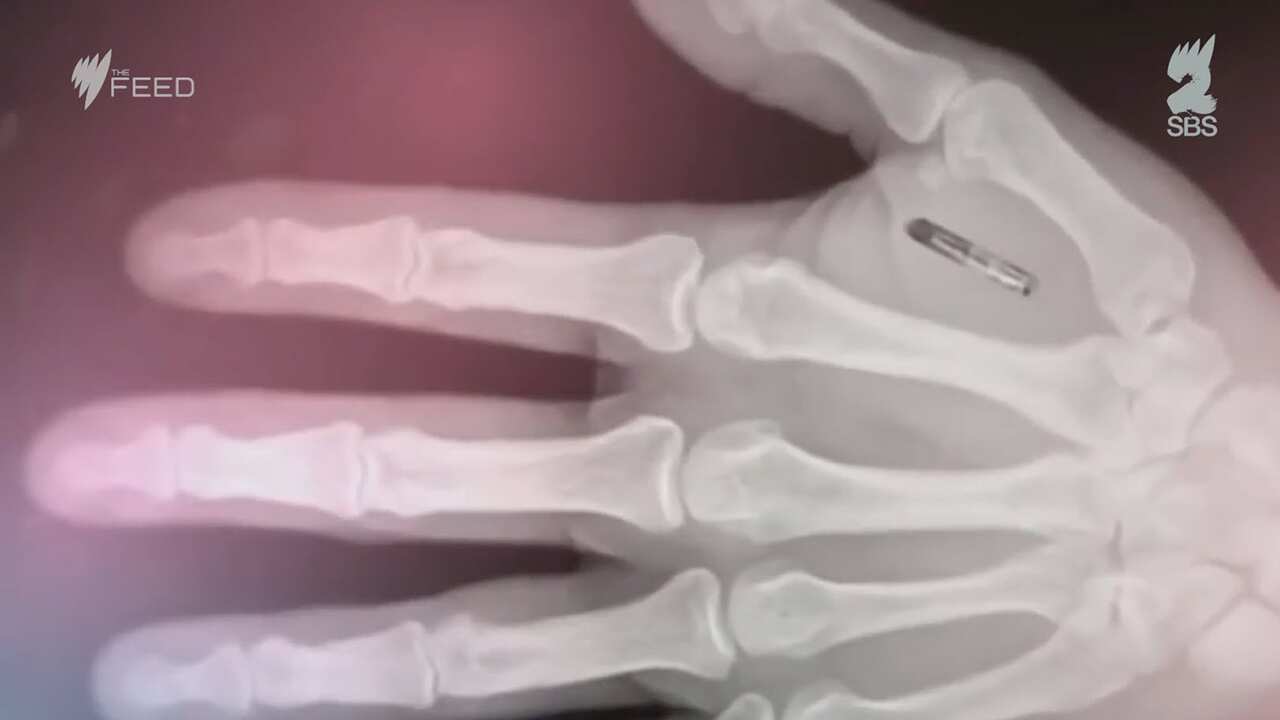

A self-described technologist, he has four RFID implants in his body that are about the size of a grain rice. These little bundles of wiring and casting of biocompatible glass sit under his skin and basically make him a little bit robot.

Graafstra is the founder and CEO of Seattle-based company Dangerous Things, which sells implantable devices like the ones he has in his body to anyone who has upwards of a spare $40.